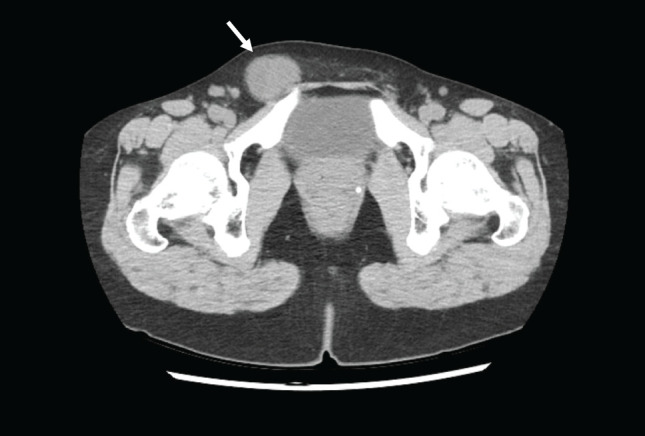

Case presentation: Here we report the case of a 42-year-old woman who presented with right inguinal tumor. The tumor had recently increased in size continuously. Computed tomography (CT) showed a homogeneous neoplastic lesion along the uterine cord in the right inguinal region and marginal resection was performed. Pathological examination revealed a well-defined tumor. And there were areas of epithelial-like tumor cells arranged in a reticular or cord-like pattern against a background of mucinous stroma, and areas of spindle-shaped cells growing in mucinous substrate with transition from epithelial cells. The nucleus was irregular in size and shape. Necrotic nests were scattered in the tumor. Immunohistological examination showed that the tumor cells were positive for epithelial membrane antigen (EMA), estrogen receptor (ER), and progesterone receptor (PgR). Alpha-smooth muscle actin (α-SMA) was slightly positive. The tumor was negative for cytokeratin AE1/AE3, p63, desmin, CD34, S100, glial fibrillary acidic protein (GFAP), and SOX10. Loss of INI1 protein expression was also confirmed. The patient was suspected of having high-grade myoepithelioma on pathological diagnosis at our hospital. However, immunohistological findings led to the diagnosis of MELTVR. The patient underwent additional wide excision and has been alive 10 months postoperatively without recurrence.